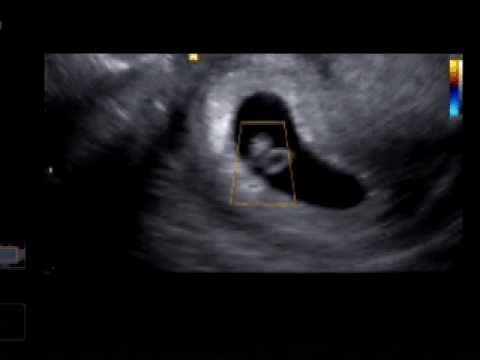

Dneska jdu v 10 na uz a krevní testy tak uvidím jak to dopadne, doufám, že je prcek v pořádku, hrozně se o něj bojím, i když jsem ho ještě ani neviděla jak vypadá.

Pak si sedl vedle a dal mi na břicho gel, no prostě UZ.

Já: Tak co?

Otočil monitor.

Já: Takže je to 100%?

Kr: Ano, jste asi v 10tt

Já: A... A je všechno v pořádku?

Kr: Ano

Ukápla mi slza štěstí.

Kr: Ještě si poslechnu srdíčko a udělám vám snímek

Pustil to a já jsem se málem roztekla.

Kr: Miminko je v nejlepším pořádku

Dal mi snímek a hned jsem si ho dala do kapsy a vrátila se do práce jakože nic.